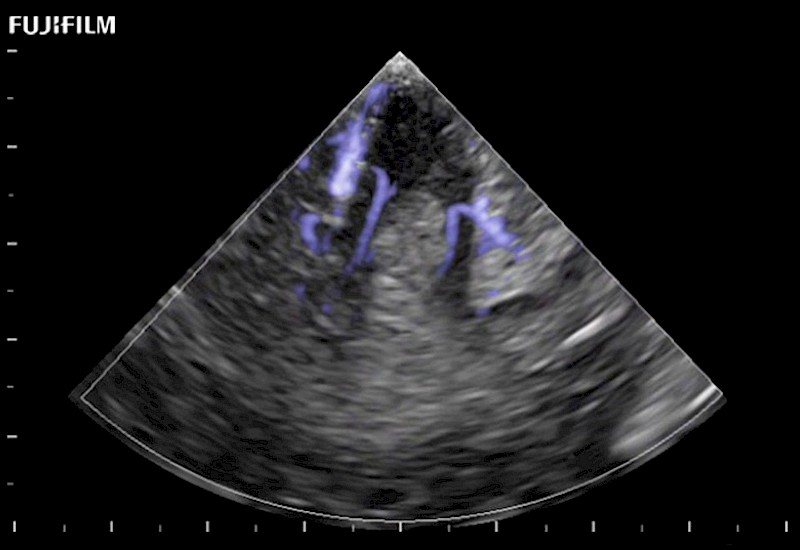

The world's only phased array burr-hole transducer that is ideal for scanning during burr-hole guidance procedures.

Main Specifications: